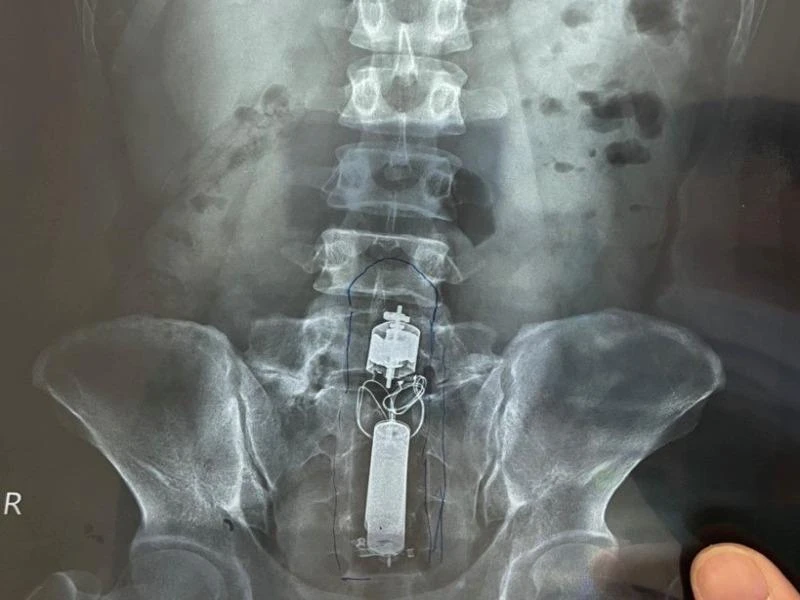

Phim chụp hình ảnh dụng cụ tình dục trong trực tràng. Ảnh: BVCC